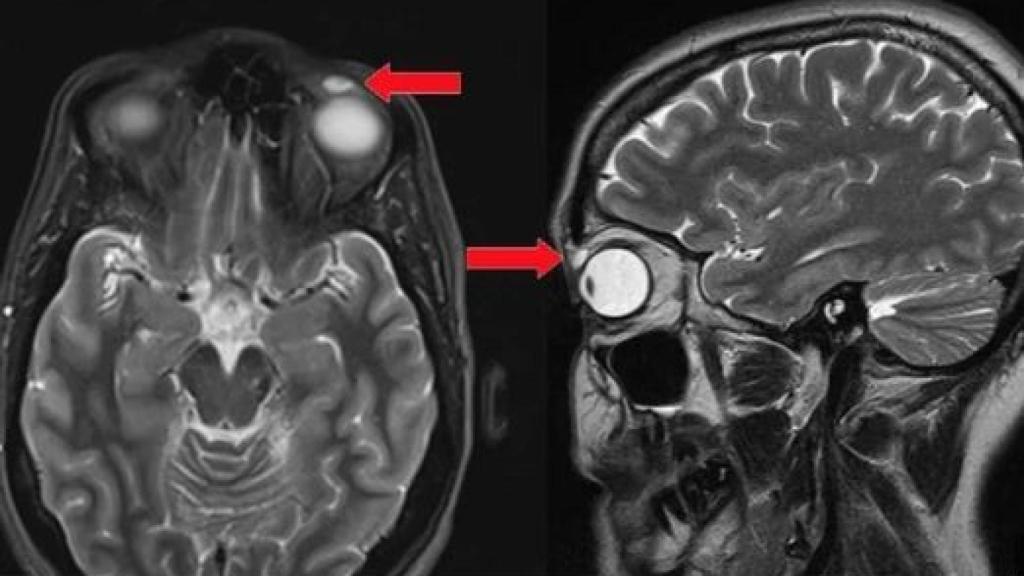

Prueba de imagen que revela la existencia de la lentilla perdida. BMJ Case Reports

Cuando se le realizó una resonancia magnética, los médicos detectaron un quiste de 8 por 4 por 6 milímetros bien definido, justo por encima del ojo izquierdo, que requirió extracción quirúrgica. La sorpresa llegó al abrir dicho quiste tras la intervención: había una lente de contacto dura pero muy frágil en su interior.